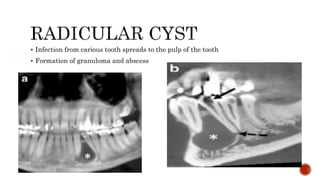

 Infection from carious tooth spreads to the pulp of the tooth

 Formation of granuloma and abscess